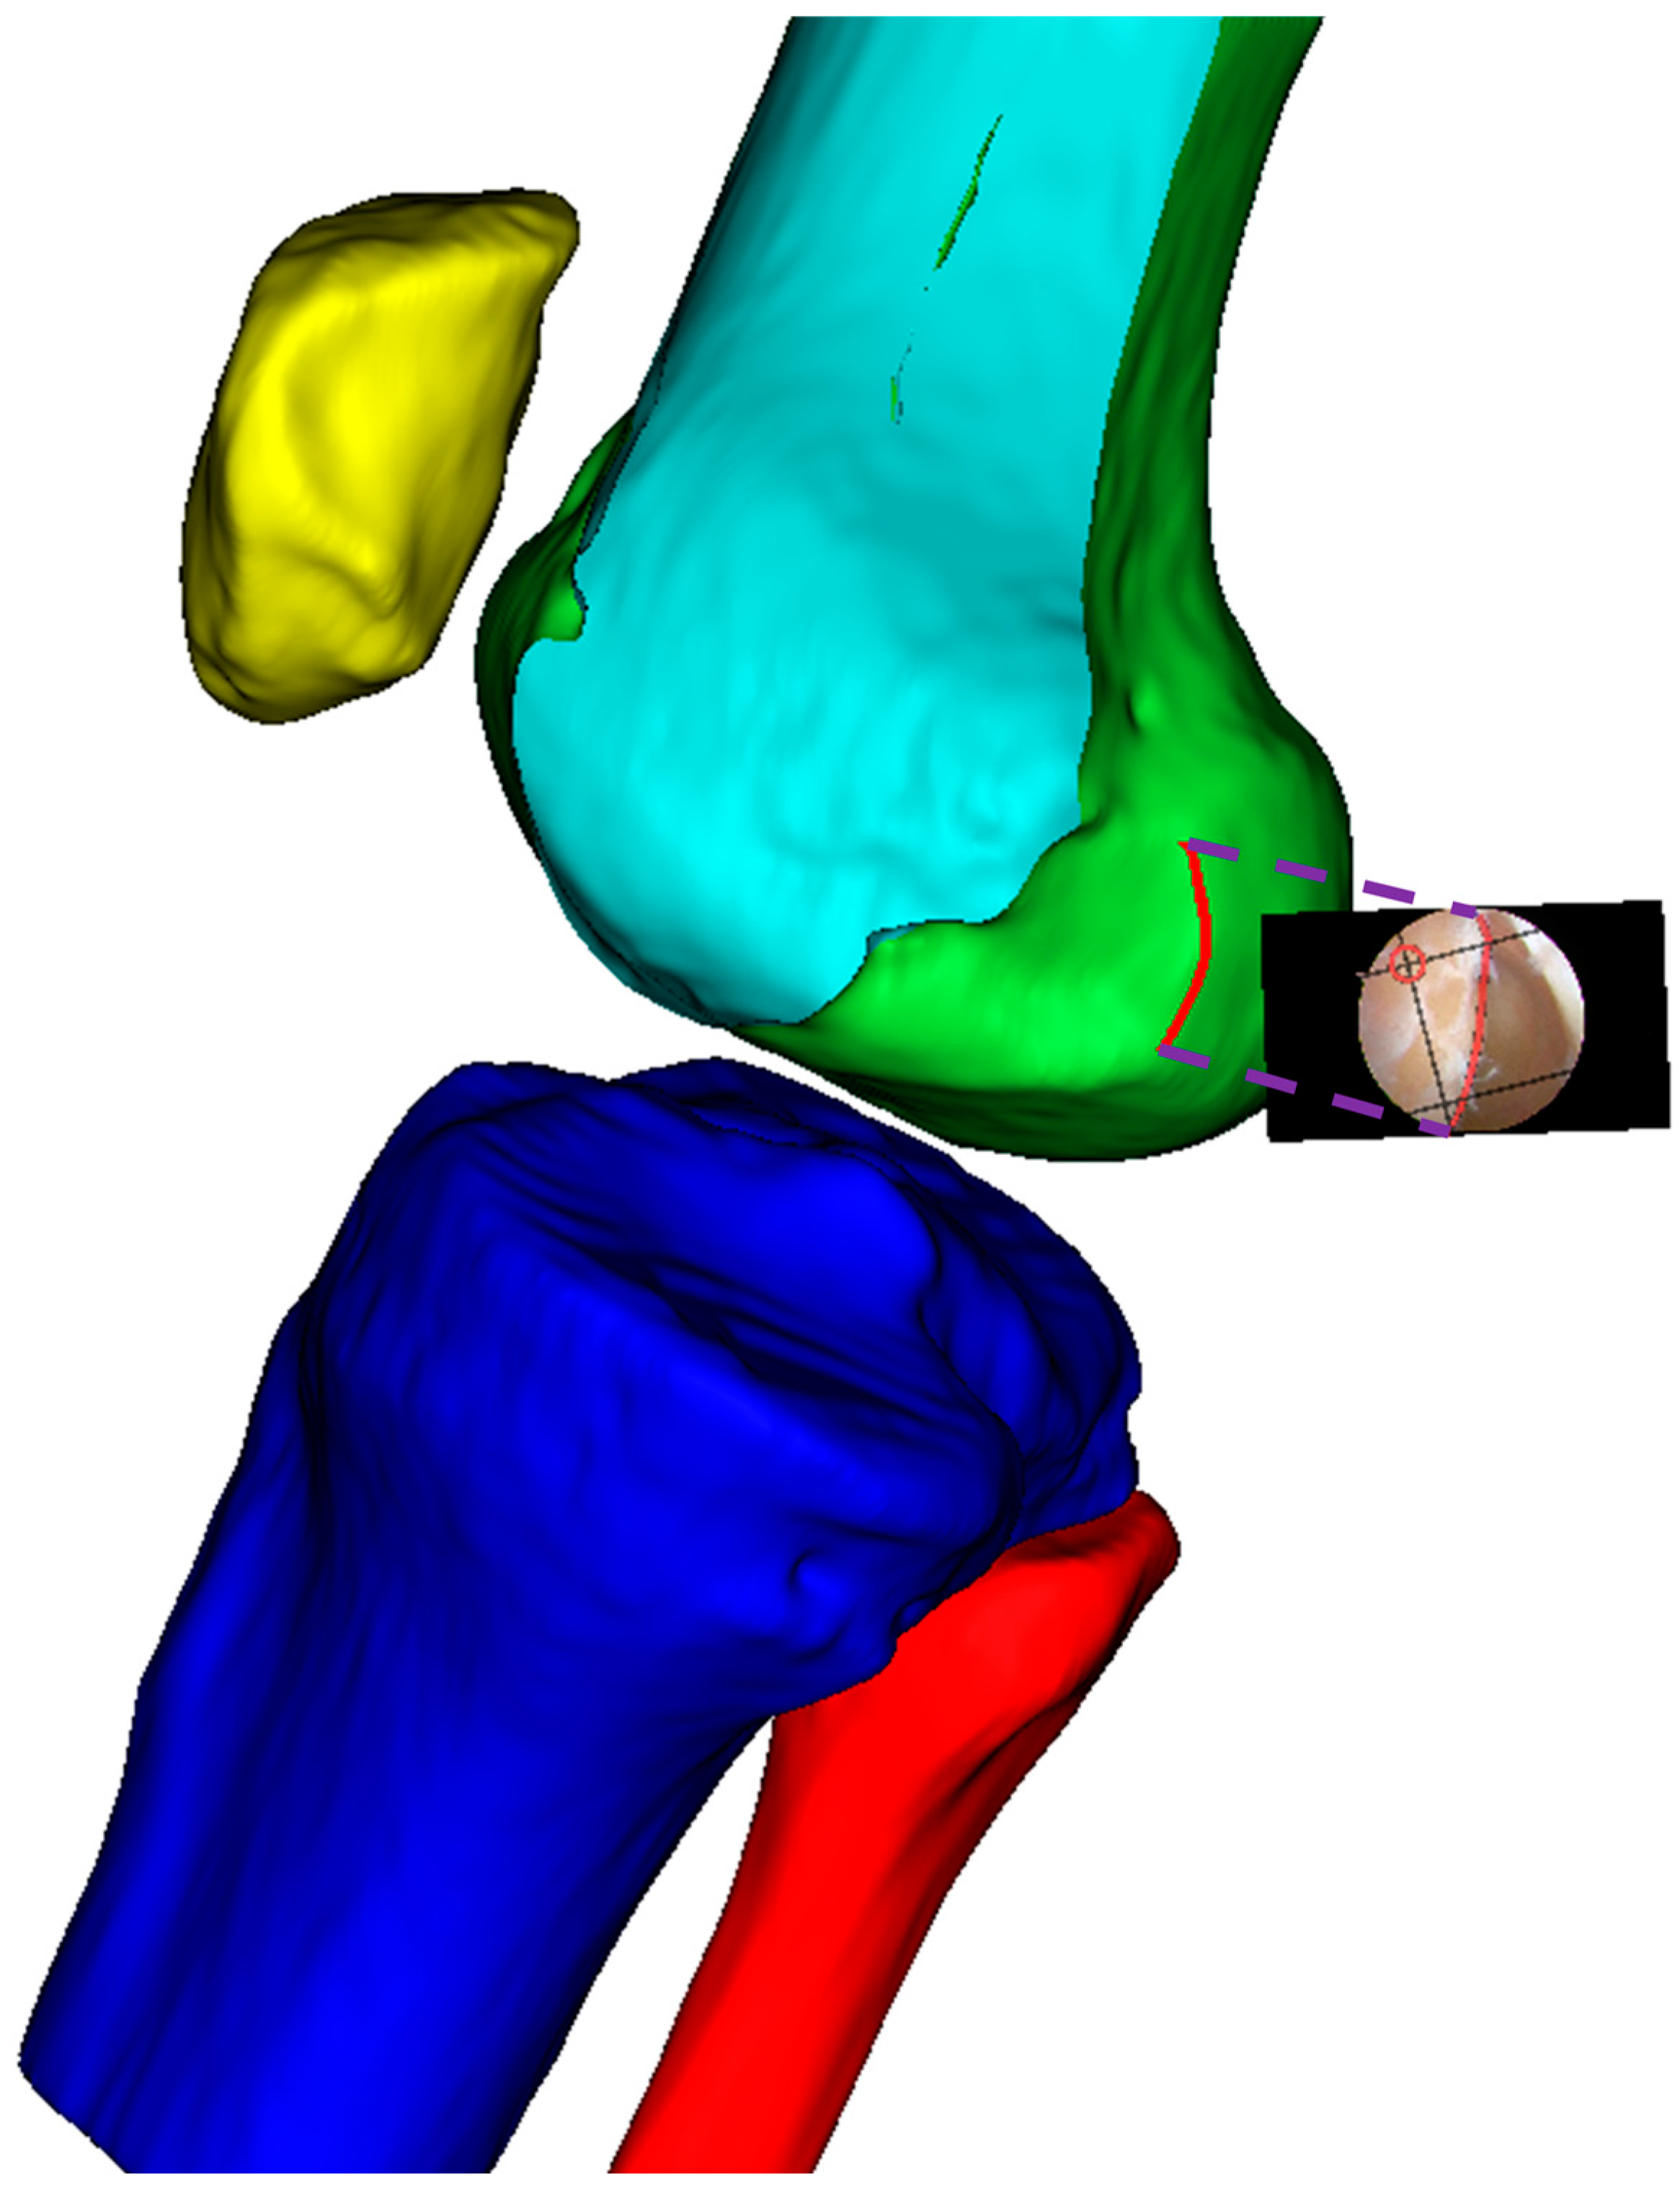

Finally, as shown in Figure 8, the modified sagittal plane is used to cut the distal femoral model, removing the medial condylar region while preserving the lateral portion. The lateral condyle holds significant anatomical and surgical importance in ACL reconstruction surgery. It provides crucial anatomical landmarks for determining the correct position of the femoral tunnel, which is essential for restoring normal knee joint mechanical function. The morphology and position of the lateral condyle offer anatomical references for surgeons to evaluate and ensure proper graft placement, thereby improving post-operative knee stability and preventing graft loosening or displacement. Moreover, precise utilization of the lateral condyle for tunnel drilling and graft fixation can reduce the risk of perioperative tissue damage and post-operative complications. Ultimately, surgeons can adapt their surgical techniques based on the specific anatomical characteristics of the patient’s lateral condyle, accommodating individual variations to improve surgical success rates and patient recovery outcomes.

Figure 8. Distal femoral resection strategy and preserved condylar geometry: (a) implementation of modified sagittal plane for distal femoral resection; (b) resulting preserved lateral condylar portion after virtual resection planning.